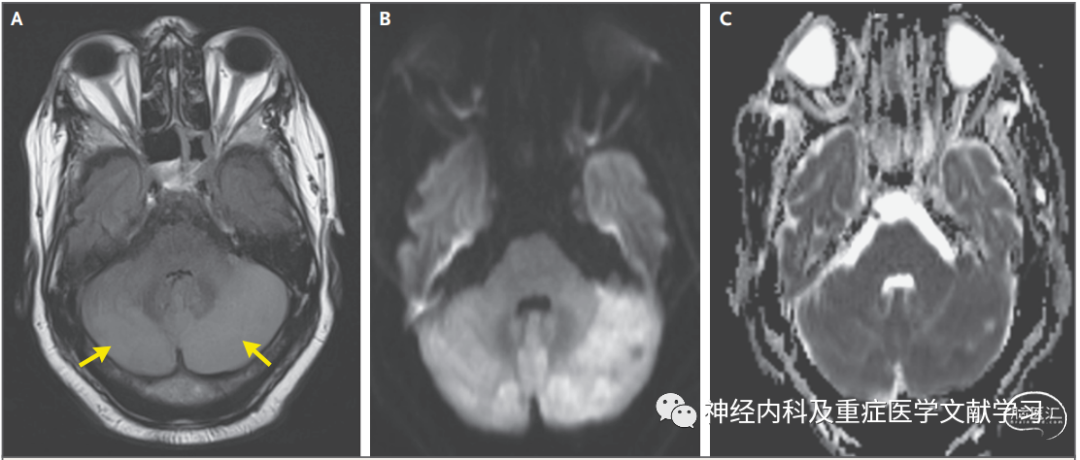

图4PRES患者非典型影像学改变

一名57岁的男子在肾移植后患有多灶性肌阵挛、2019冠状病毒病和慢性肾脏疾病,目前正在接受免疫抑制治疗。图A显示患者颅脑轴向MRI FLAIR图像,小脑半球弥漫性融合信号改变(箭头)。B图为弥散加权图像,这些区域的信号变化不对称。表观扩散系数图像(C组)未显示这些区域的变化,提示脑组织没有梗死。